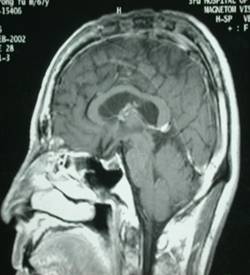

病例1-颅内巨大脑膜瘤

女性,65岁,因右半身轻偏瘫1个月入院。查MRI示:左顶叶窦镰旁脑膜瘤。如下:

术前照片